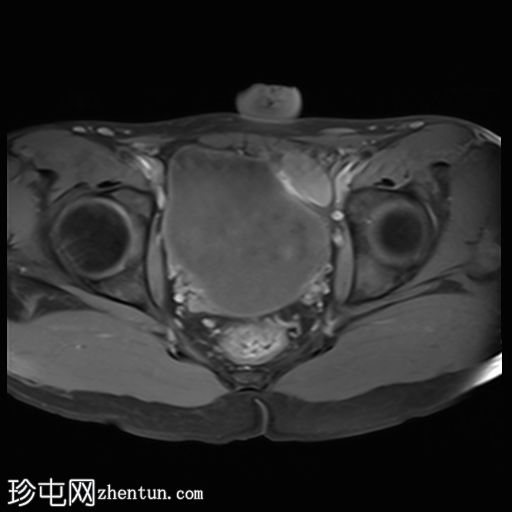

MRI

冠状位

T2加权像

轴位

轴位 T1加权像

脂肪抑制像

轴位 T2加权像

DWI

ADC

左侧睾丸未在阴囊内显影,而是在盆腔内,膀胱左壁外侧可见。左侧隐睾形态、大小和信号强度相对正常。

右侧睾丸位于右侧阴囊内,大小、形态和信号强度均正常。

隐睾症是指一侧或双侧睾丸未位于阴囊内。其表现形式包括隐睾、异位睾丸或萎缩/缺失睾丸。该患者的左侧睾丸异位位于盆腔内,膀胱左壁外侧,而右侧睾丸则位于阴囊内。准确定位至关重要,因为手术方案的选择取决于睾丸的位置。